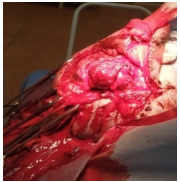

Figure 1: First trepanation of the skull. After opening the dura mater, the purulent discharge is cleaned.

In Fig. 1 – craniotomy, sanitation of purulent discharge from under the dura mater. In Fig. 2 – repeated craniotomy, the bone window was about 12x10 cm. A section of the prolapsed brain is visible. The brain prolapse from the previous trepanation has been revised, partially performed encephalotomy, brain debris removed.